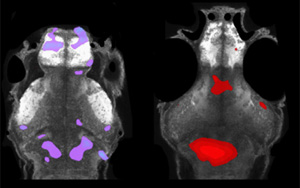

Science子刊:世界首個(gè)能抵御致死性細(xì)菌感染的mRNA疫苗問(wèn)世

近日,一篇發(fā)表在國(guó)際雜志Science Advances上題為“A single-dose F1-based mRNA-LNP vaccine provides protection against the lethal plague bacterium”的研究報(bào)告中,來(lái)自以色列特拉維夫大學(xué)等機(jī)構(gòu)的科學(xué)家們通過(guò)研究開(kāi)發(fā)出了首個(gè)基于mRNA的疫苗,其或能100%有效抵御一種對(duì)人類致死的細(xì)菌。